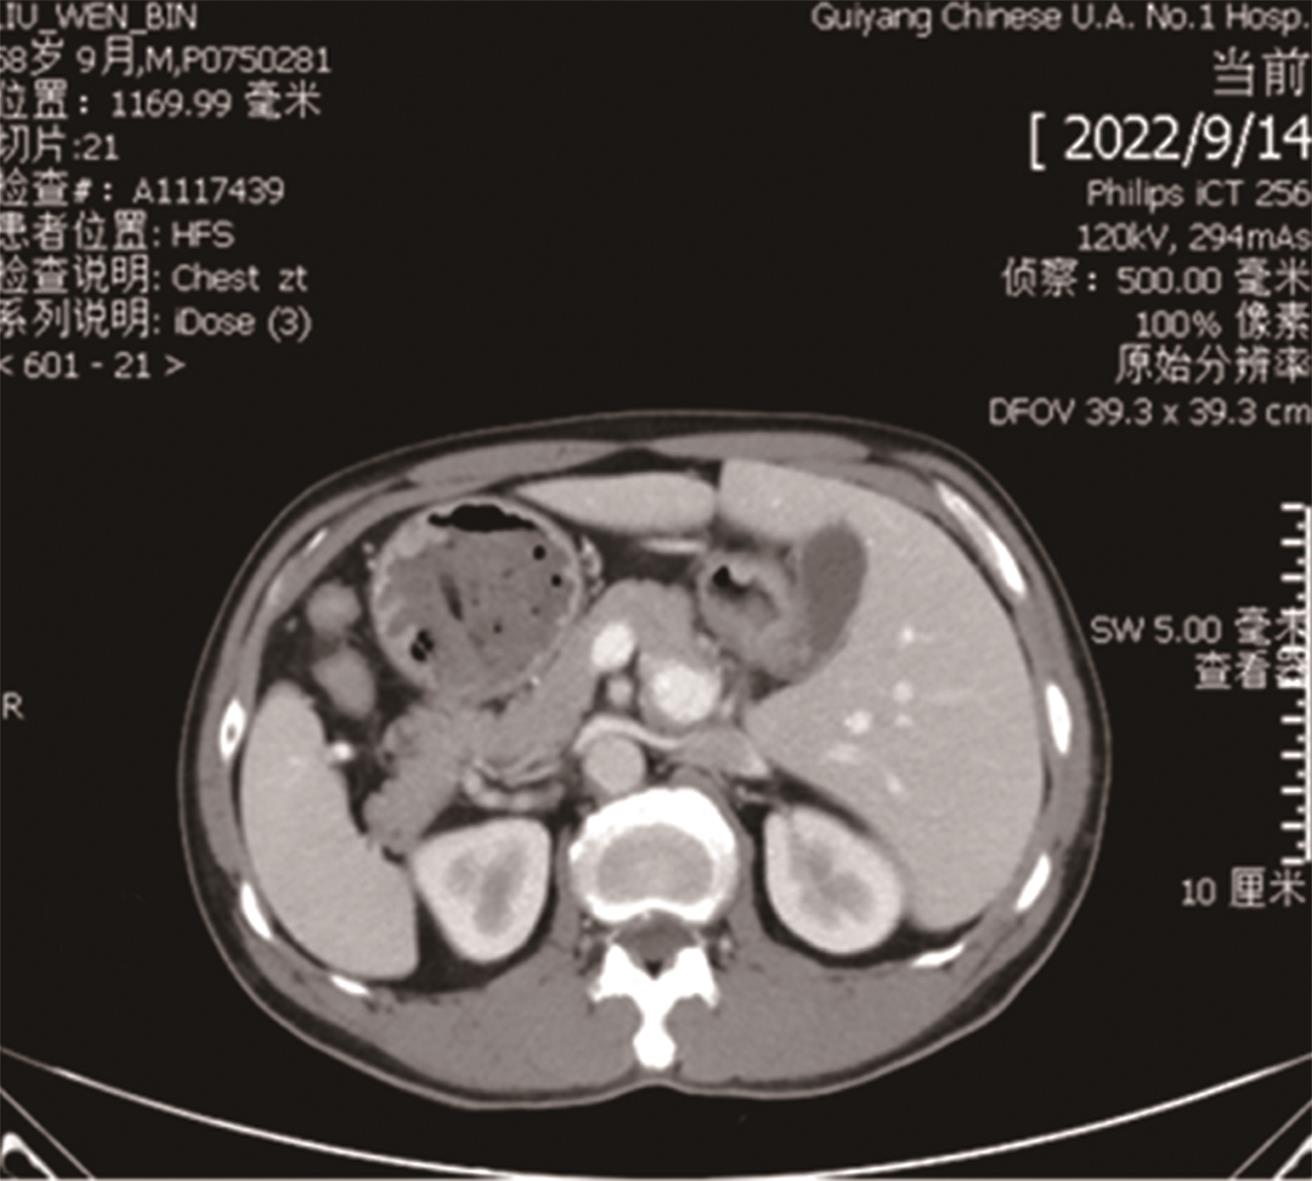

• “镜面人”保留左结肠动脉腹腔镜低位直肠癌根治术1例

2023, 48(7):853-856. DOI: 10.13406/j.cnki.cyxb.003278

摘要 (87) HTML (56) PDF 3.64 M (283) 评论 (0) 收藏